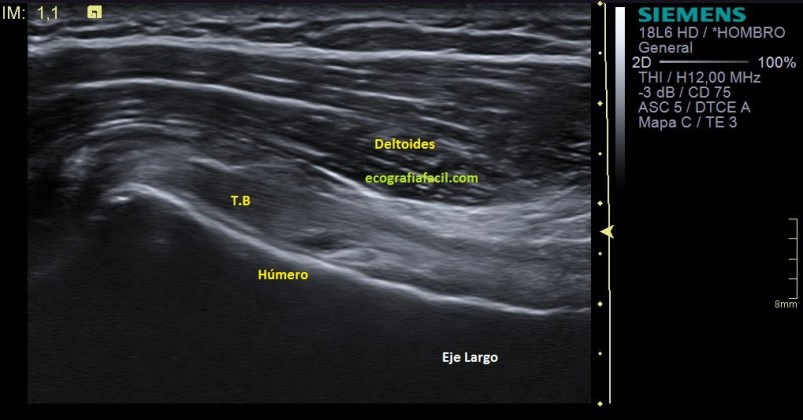

La imagen número 3 corresponde al corte en eje largo, mucho cuidado, siempre que tengamos el tendón del bíceps luxado, este se irá hacia medial, por eso, en eje largo vamos a encontrar la ecoestructura ligeramente hacia la axila, hacia medial.